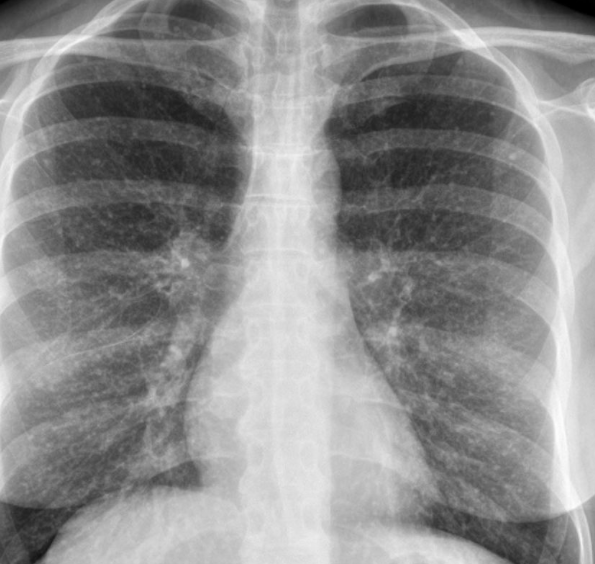

Multifocal peripheral consolidation/ground glass

1. Cryptogenic organising pneumonia (more lower lobe. Subpleural sparing)

2. Eosinophilic pneumonia (upper lobe more than lower. Can look like pulmonary oedema)

Eosinphilic